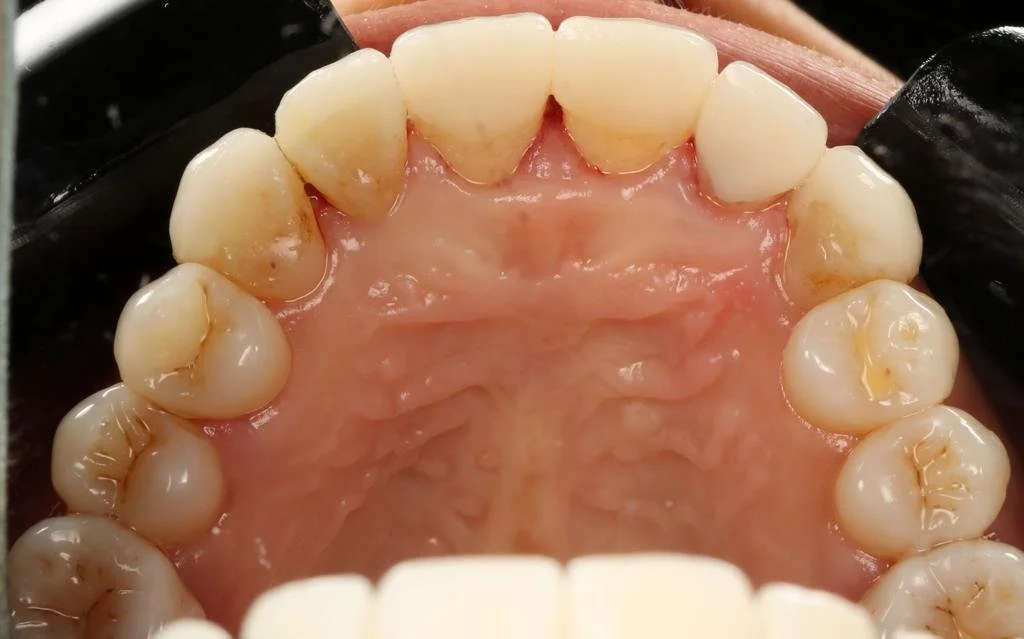

Cerec Reshape and Stain Graze